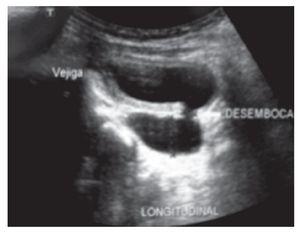

Fue recibido en el Instituto a los cinco meses de edad, durante esta visita se realizó ultrasonido renal y vesical, observando un gran divertículo vesical a la izquierda de la vejiga, cuyo tamaño era de dimensiones similares a la vejiga (Figura 1). La uretrocistografía confirmó el hallazgo del ultrasonido (Figura 2).

Figura 1.Ultrasonido con evidencia del divertículo proveniente de vejiga, con cuello de divertículo ubicado en piso vesical.